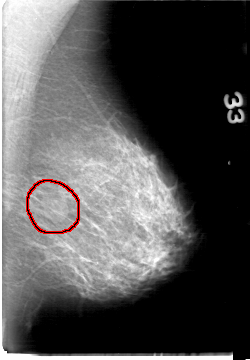

D_4058_1.LEFT_CC

LEFT_CC LINES 5386 PIXELS_PER_LINE 3316 BITS_PER_PIXEL 12 RESOLUTION 43.5 OVERLAY

FILE: D_4058_1.LEFT_CC.OVERLAY

TOTAL_ABNORMALITIES 1

ABNORMALITY 1

LESION_TYPE MASS SHAPE OVAL MARGINS OBSCURED

ASSESSMENT 0

SUBTLETY 3

PATHOLOGY BENIGN

TOTAL_OUTLINES 1

BOUNDARY